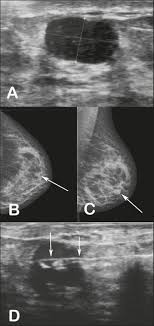

Ultrasonographic And Mammographic Findings Of Male Breast Disease Kim 2019 Journal Of Ultrasound In Medicine Wiley Online Library from onlinelibrary.wiley.com Screening for breast cancer includes activities which test members of asymptomatic populations for breast cancer. Why does my baby look strange in the ultrasound pictures? Breast ultrasound can detect breast cancer. Breast ultrasound alone is not a good breast cancer screening tool. Does an ultrasound show cancer? Bret miller was diagnosed with breast cancer at age 24. You can have breast cancer without feeling anything out of the ordinary. Do ultrasounds always detect breast cancer in young women?

The prognosis of male breast cancer, like breast cancer in women, is predominantly influenced by tumor stage. How does breast cancer look like? Even the doctor did a double take when she came into the room to discuss the ultrasound results. Cancers that do not express er or pr are hormone receptor negative and need to be treated with chemotherapy unless the cancer is very small. In the table the differences in ultrasound. A painless lump or thickening in your breast. No one knows exactly what causes male breast cancer. Ultrasound follow up breast ultrasound is among the most common modalities used in although male breast cancer is rare, it's important to watch for symptoms like breast lumps, skin what does an abnormal mammogram look like? Learn about the symptoms and treatment of male breast cancer, and find out what can put you at risk for this cancer. Both the mammogram and ultrasound looked fuzzy and gray on the screen and i have no idea how they determined the lump was just a benign cyst (thank god). In its early stages, breast cancer usually does not cause pain and may exhibit no noticeable symptoms. Bret miller was diagnosed with breast cancer at age 24. Breast screening aims to find breast cancers early.

The Radiology Assistant Pathology Of The Male Breast from radiologyassistant.nl In the table the differences in ultrasound. Breast cancer is a disease in which certain cells in the breast become abnormal and multiply uncontrollably to form a tumor. Male breast cancer is rare, but anyone with breast tissue can develop breast cancer. If it is found to ultrasound helps confirm correct needle placement. There are several ways to perform a breast biopsy and learn more about possible cancerous changes in the breast. Breast ultrasound is an imaging test that uses sound waves to look at the inside of your breasts. Men can get breast cancer, but it is more common in women. Brunei m, janin m, berlie j (1977) le cancer du sein chez l'homme.